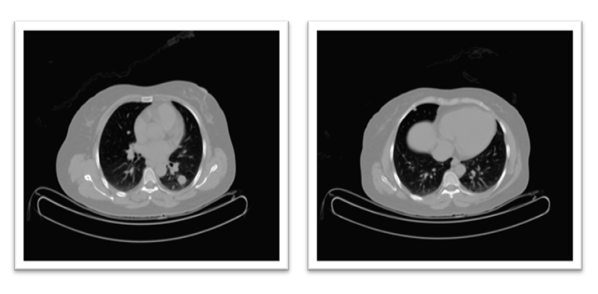

Postoperatively, the patient’s immediate recovery was unremarkable. However, approximately four weeks after surgery, she developed right-sided pelvic discomfort. MRI of the abdomen and pelvis was performed in May 2023 to assess any postoperative complications or residual disease. This imaging revealed a sizable mass in the right pelvic cavity (~8×6×4 cm) in the region of the hysterectomy bed, raising concerns for either local residual tumour or early recurrence. Further evaluation using chest imaging identified multiple bilateral lung nodules (up to 1-2 cm in diameter) that were suspicious for metastatic lesions (Figure 1).

No liver lesions or other distant metastases were seen on abdominal imaging. Based on these findings, the patient was diagnosed with metastatic uterine sarcoma (Stage IV) approximately one month after her initial surgery. To achieve a more accurate assessment of the tumour and expand therapeutic options, ER, PR, AR, Her-2 (Human epidermal growth factor receptor-2), PD-L1 (Programmed Death Ligand-1), and Ki-67 were analysed in the resected tissues.